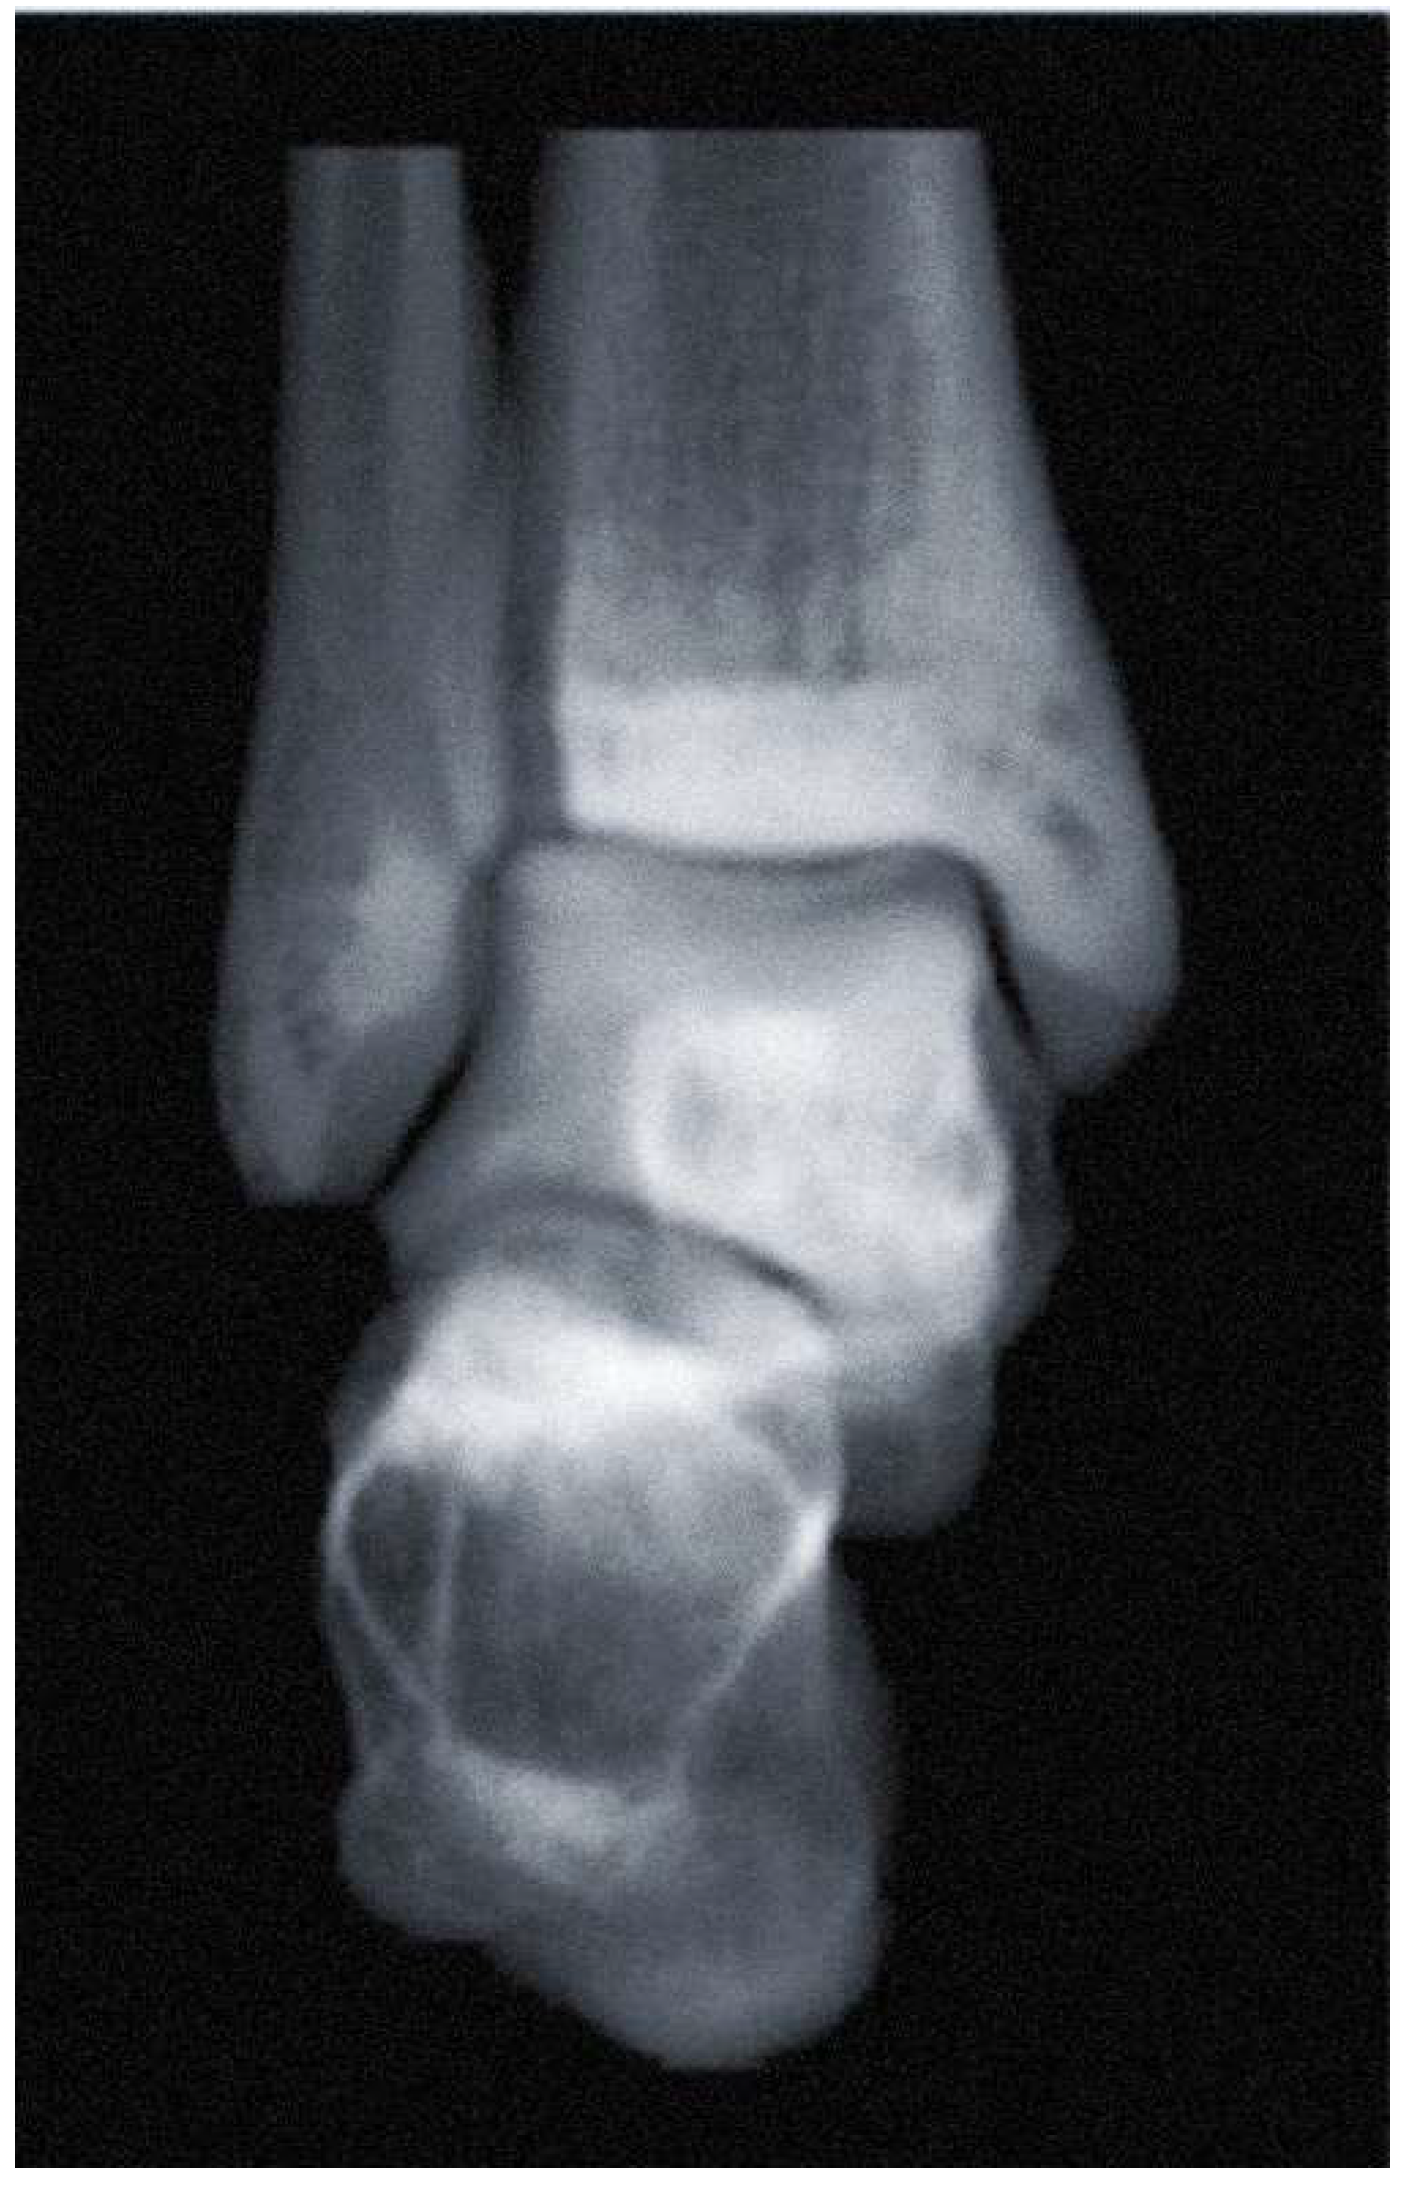

In addition, several studies attempted to diagnose ankle OA by measuring the joint space width (JSW) using WBCT. Wiley et al first applied JSW to evaluate the joint space narrowing in posttraumatic ankle osteoarthritis, which showed good reliability and reproducibility [11]. The measurement was performed in a single-value, 2D manner made at selected locations. With the development of technology, however, software-driven 3D geometric measurements of the distance between bone surfaces became possible (Figure 2) [12]. Although its automated imaging process of the measurements needs to be improved, 3D JSW mapping may enhance intuitive visualization of the ankle joint biomechanics. Furthermore, it provides highly sensitive monitoring of joint space narrowing, which may be used as an alternative indicator for progression in joint disease.

Figure 2. Bounding box method to detect the joint width narrowing using automated intelligence (AI) with the Xelis 3D imaging software (INFINITT Healthcare, Korea).